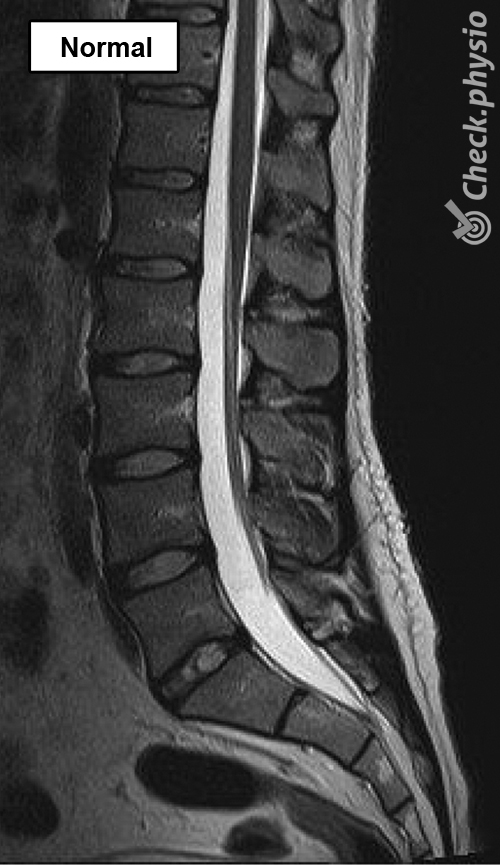

Nettbasert fysioterapi for Lumbal spinal stenose

Har du hatt plager en stund? Og blir det ikke bedre selv om du hviler eller unngår smertefulle bevegelser? Da er det lurt å gjøre noen øvelser hver dag for å redusere plagene permanent.

Vårt nettbaserte treningsprogram for Lumbal spinal stenose er satt sammen av erfarne fysioterapeuter. Tilnærmingen er dokumentert effektiv og vitenskapelig forankret.